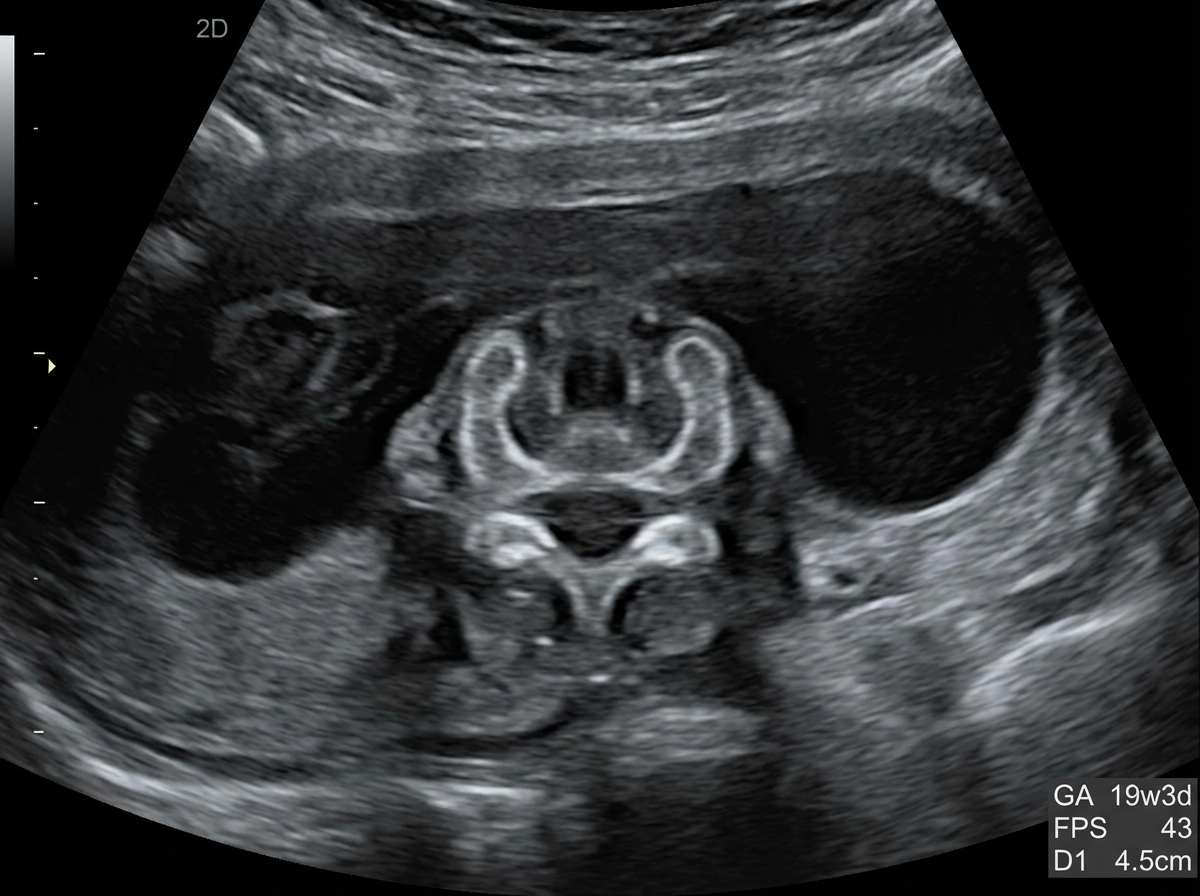

A 25-year-old pregnant woman, at 18 weeks of gestation, undergoes a routine ultrasound scan. The ultrasound images provided show below. Based on the imaging findings, what is the most likely diagnosis?

Explanation: ***Spina bifida*** - The ultrasound image shows a **defect in the posterior elements of the fetal spine**, with characteristic splaying or widening of the vertebral arches. - This is a **neural tube defect** resulting from incomplete closure of the spinal column during embryonic development. - Associated findings on prenatal ultrasound may include the **"lemon sign"** (scalloping of frontal bones) and **"banana sign"** (abnormal cerebellar shape). - Spina bifida is typically detected on **second-trimester anatomy scan** (18-20 weeks). *Anencephaly* - This condition involves the **absence of a major portion of the brain, skull, and scalp** due to failure of anterior neural tube closure. - On ultrasound, anencephaly presents with **absent calvarium above the orbits** and absent cerebral hemispheres, which is distinctly different from a spinal defect. - This would be a **cranial abnormality**, not a spinal column defect. *Encephalocele* - An **encephalocele** is a protrusion of brain tissue and meninges through a defect in the skull, most commonly at the **occipital region**. - On ultrasound, this appears as a **cranial mass** extending beyond the skull contour, not a spinal defect. *Holoprosencephaly* - This condition results from **failure of forebrain (prosencephalon) to divide properly** into two hemispheres. - Ultrasound findings include **single ventricle**, fused thalami, and absent midline structures, often with associated **facial anomalies**. - The imaging would show **brain abnormalities**, not spinal column defects. *Iniencephaly* - This is a rare **neural tube defect** characterized by extreme retroflexion of the head with severe spinal defects in the cervical and thoracic regions. - On ultrasound, iniencephaly shows the fetal head in extreme **hyperextension** with the face looking upward, creating a characteristic "stargazing" appearance. - This differs from the typical spinal defect pattern seen in spina bifida.